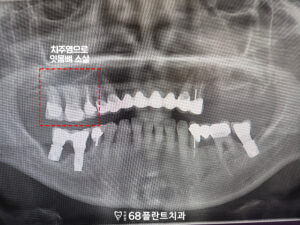

확인해 보니,

전체적으로 치료한 부위가 많았으나

관리가 제대로 되지 않아

치주염이 발생하였고,

그로 인해 잇몸뼈가 녹아

뼈가 소실되었습니다.

이로 인해 치아의 흔들림과

불편함이 발생했으며,

결국 임플란트 치료가 필요하다는

판단을 내리게 되었습니다.

또한 오른쪽 아래 임플란트와

치아도 염증으로 인해 뼈가 녹아

제 기능을 못하고 있었습니다.